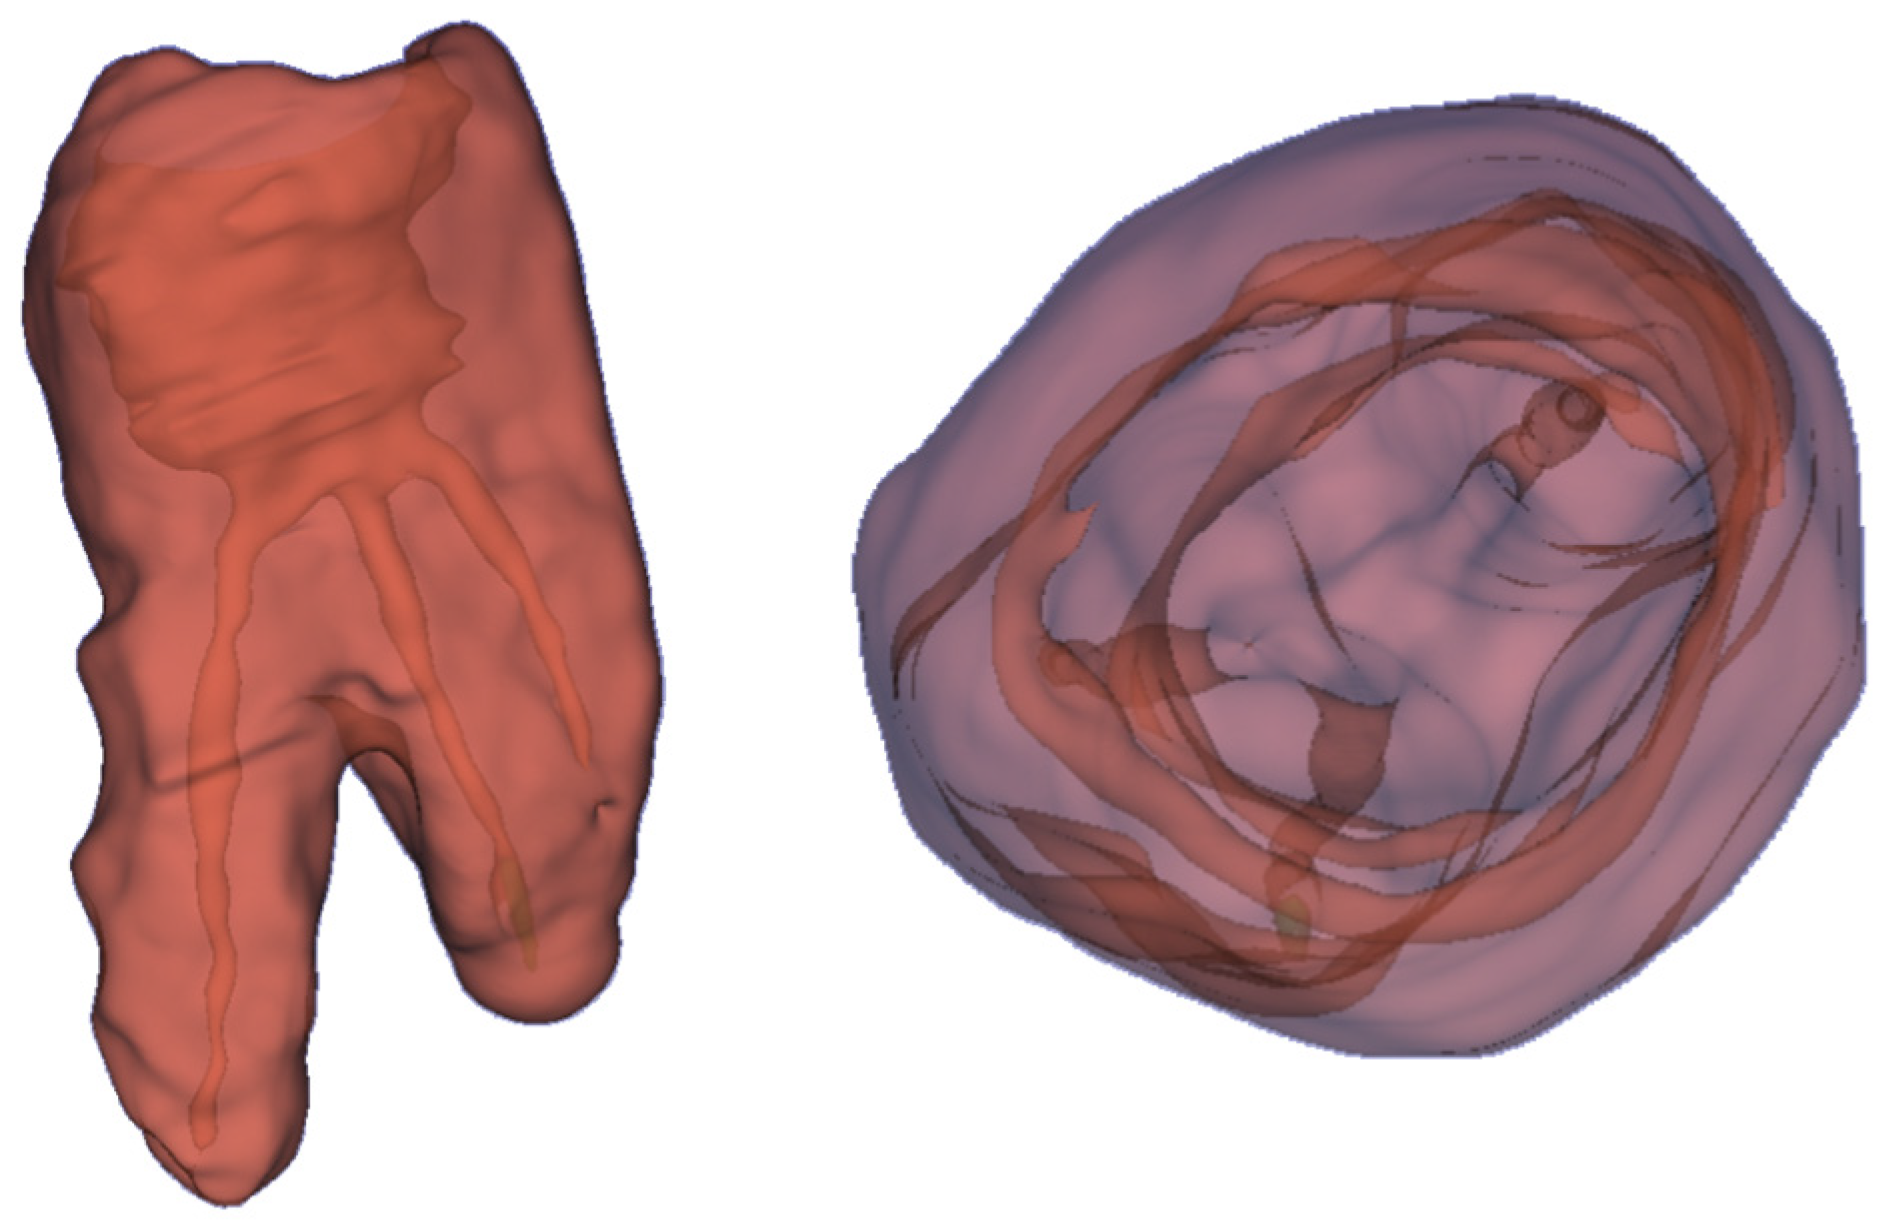

Various types of software and hardware tools are required to develop and visualize holographic 3D models. In terms of hardware, the system is designed to run on Microsoft HoloLens 2. The structural models of teeth and root canals are reconstructed by a developed Python application and the models are exported into Unreal Engine (Epic Games, Potomac, MD, USA). To create the holographic 3D models of patients’ teeth, which are presented in Figure 5, DICOM RAW data from CT scans were used. By applying semi-automated algorithms, the CT scan is segmented. Every elementary volume component (i.e., voxels or Hounsfield units) of the CT scan is labeled manually and then processed. Here, the fill-between-slices algorithm was used. The application, which enables the creation of 3D holograms, was written in Python, see Figure 6. In the first step, a CT scan (DICOM data) was loaded. Next, each layer was reviewed to obtain the required range of minimal and maximal values for the entire CT scan. The values obtained are applied to select the appropriate range to obtain the best quality model. For example, the range of 0–50,000, where 0 denotes a black color and 50,000 white colors. The created range selection enables us to decide which pixels should be skipped in the generated model. It can be compared to printing black pictures on white paper. The printer is only placing black ink in black spots on white paper and skips everything where it should print in white color. Creating 3D models is the same situation. We decide which color values from the DICOM pictures should be used for creating the model and which are skipped as empty spaces.

In Figure 6, the model is created with values in the range of 2350–32,246, the selected pixels are marked red on an example preview of one CT layer. The values can be amended until the 3D model preview returns the best-quality model. Following that, we can run “cleaning” and smoothing algorithms. The final result is converted into OBJ format which is used to export the model to Microsoft HoloLens 2. To achieve the best quality and performance, a new HoloLens 2 project is created using the Unreal Engine application. Then, the Unreal new HoloLens 2 project obj file is configured with the created model. Next, we need to add appropriate lighting to view the model correctly and save the project at the end so it can be installed and run on a HoloLens 2 device.

Figure 5. The 3D holograms of the tooth, with visible root canals.